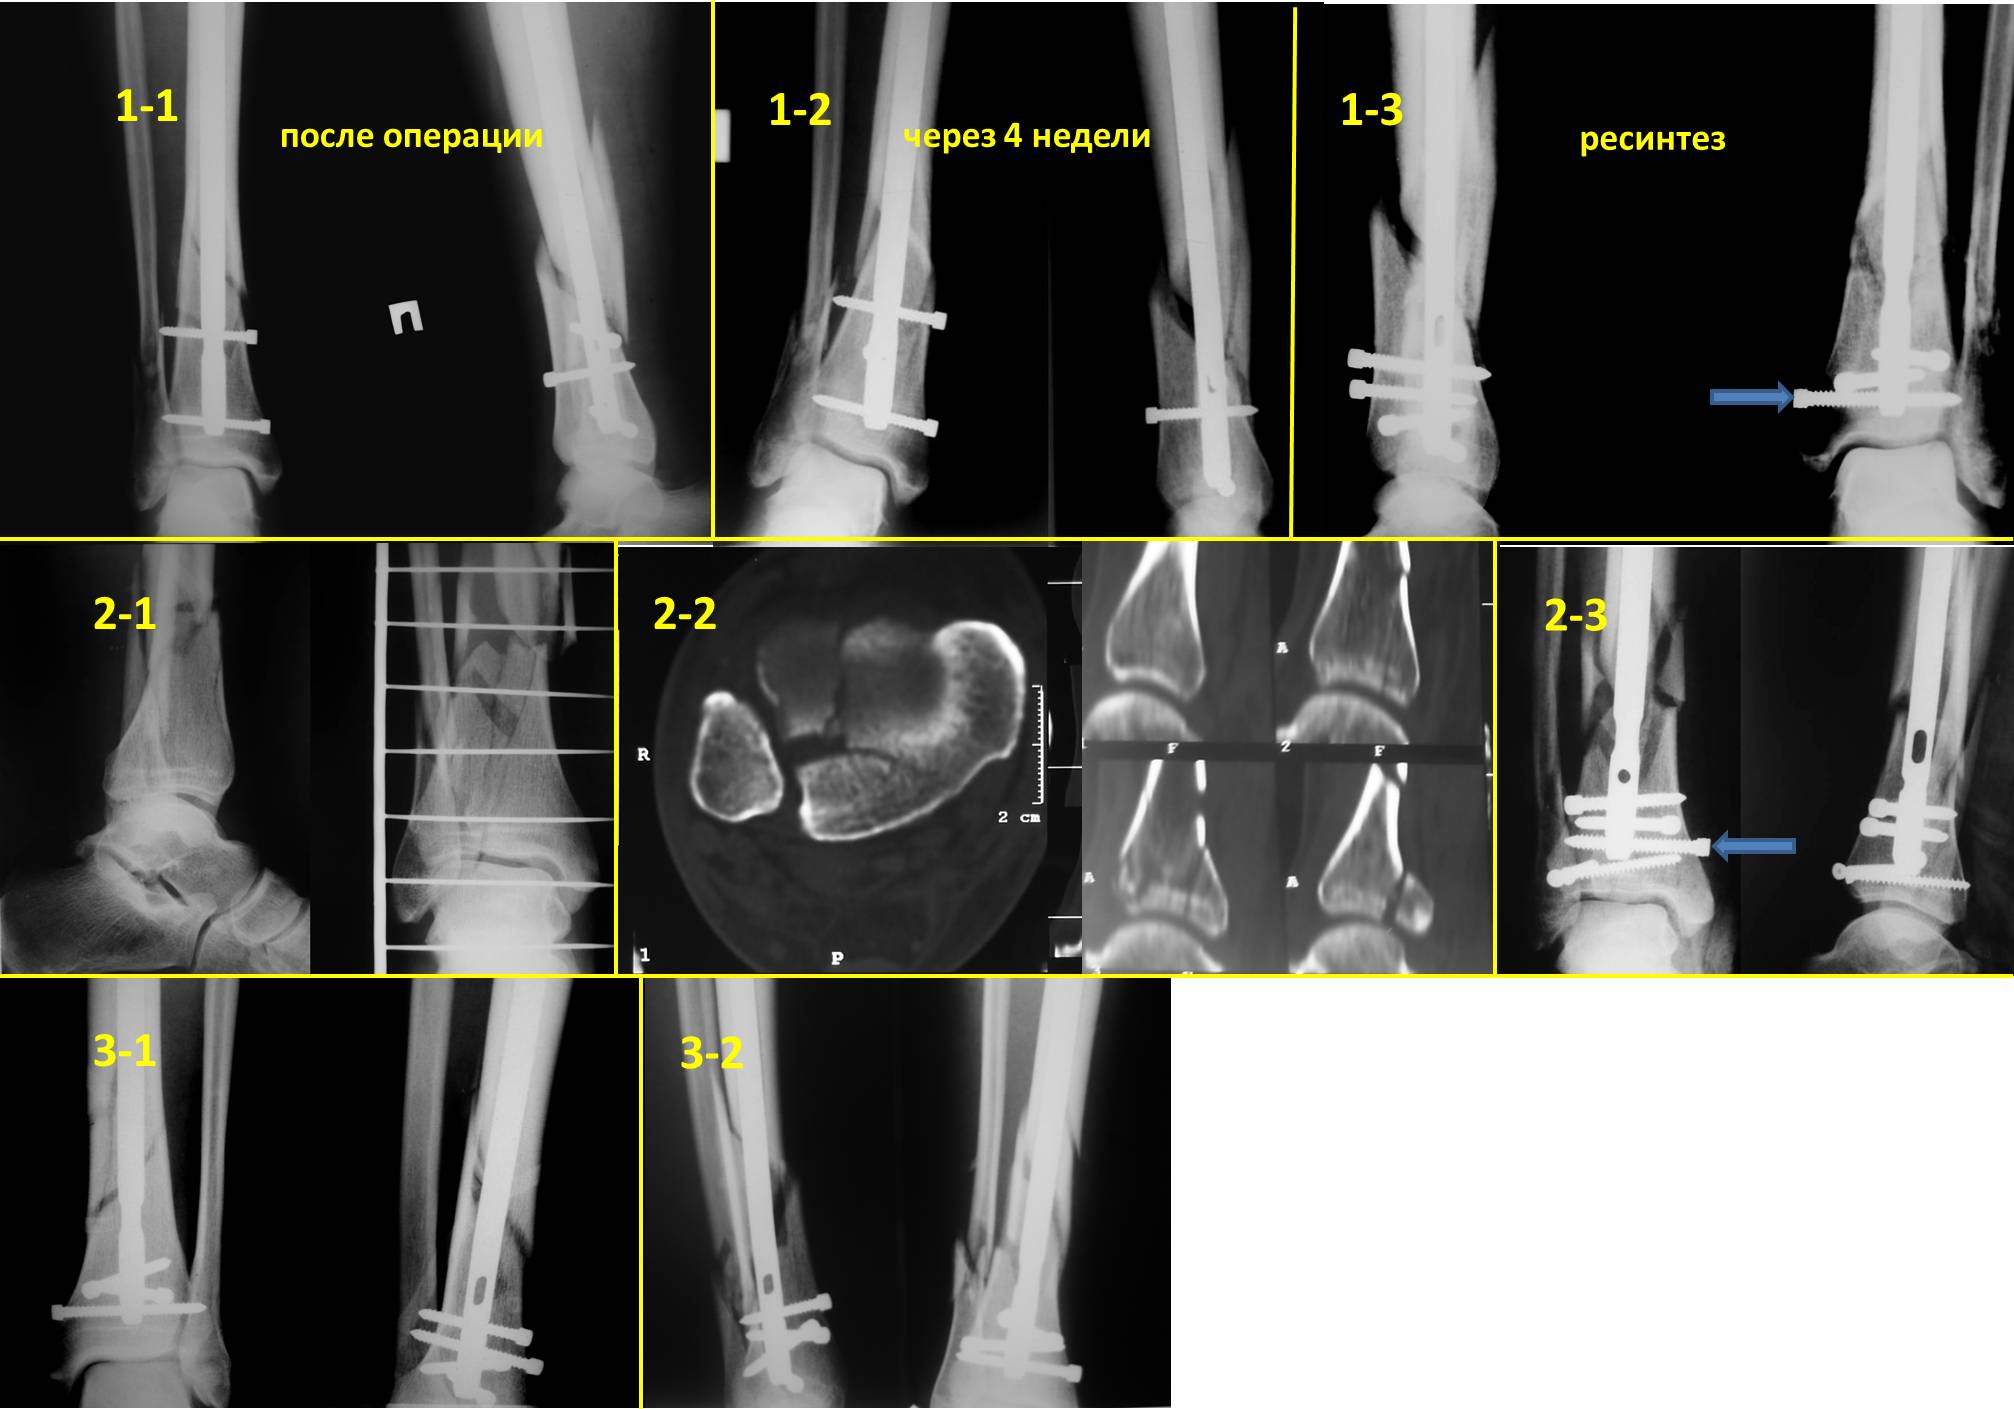

Очень интересная тема – дистальное блокирование при инфраистмальных переломах. К сожалению, аргументировано её осветить не представляется возможным в жёстких рамках поста. С моей точки зрения, неадекватное дистальное блокирование при инфраистмальных переломах большеберцовой кости является наиболее частой причиной неудач при интерлокинге. Можно ожидать проблем, если блокирование таких переломов выполняется только во фронтальной плоскости. Даже третий блокирующий винт, проведенный в сагиттальной плоскости, не всегда гарантирует необходимую стабильность (пример 1-1 – 1-3 во вложенном файле). Нестабильность фиксации случается, как правило, из-за того, что диаметр блокирующих винтов меньше диаметра блокирующих отверстий стержня, что позволяет блокирующим винтам (а значит и дистальному отломку) отклонятся от перпендикулярного положения относительно стержня. Чем больше разница в диаметрах, тем больше угол возможного отклонения. Несколько большую стабильность обеспечивают блокирующие винты, заворачивающиеся в стержень (отмечены стрелками). Мы для себя взяли за правило выполнять дистальное блокирование всех инфраистмальных переломов минимум тремя винтами, проведенными в разных плоскостях (пример 2-1 – 2-3 во вложенном файле). А с учётом того что мы не ограничиваем нагрузку в послеоперационном периоде и с целью уменьшения вероятности перелома блокирующих винтов при нагрузке - стандартная процедура дистального блокирования состоит во введении четырёх блокирующих винтов введенных в разных плоскостях (пример 3-1 – 3-2 во вложенном файле).

После применения такой методики не отмечено случаев несращения после интерлокинга инфраистмальных переломов.